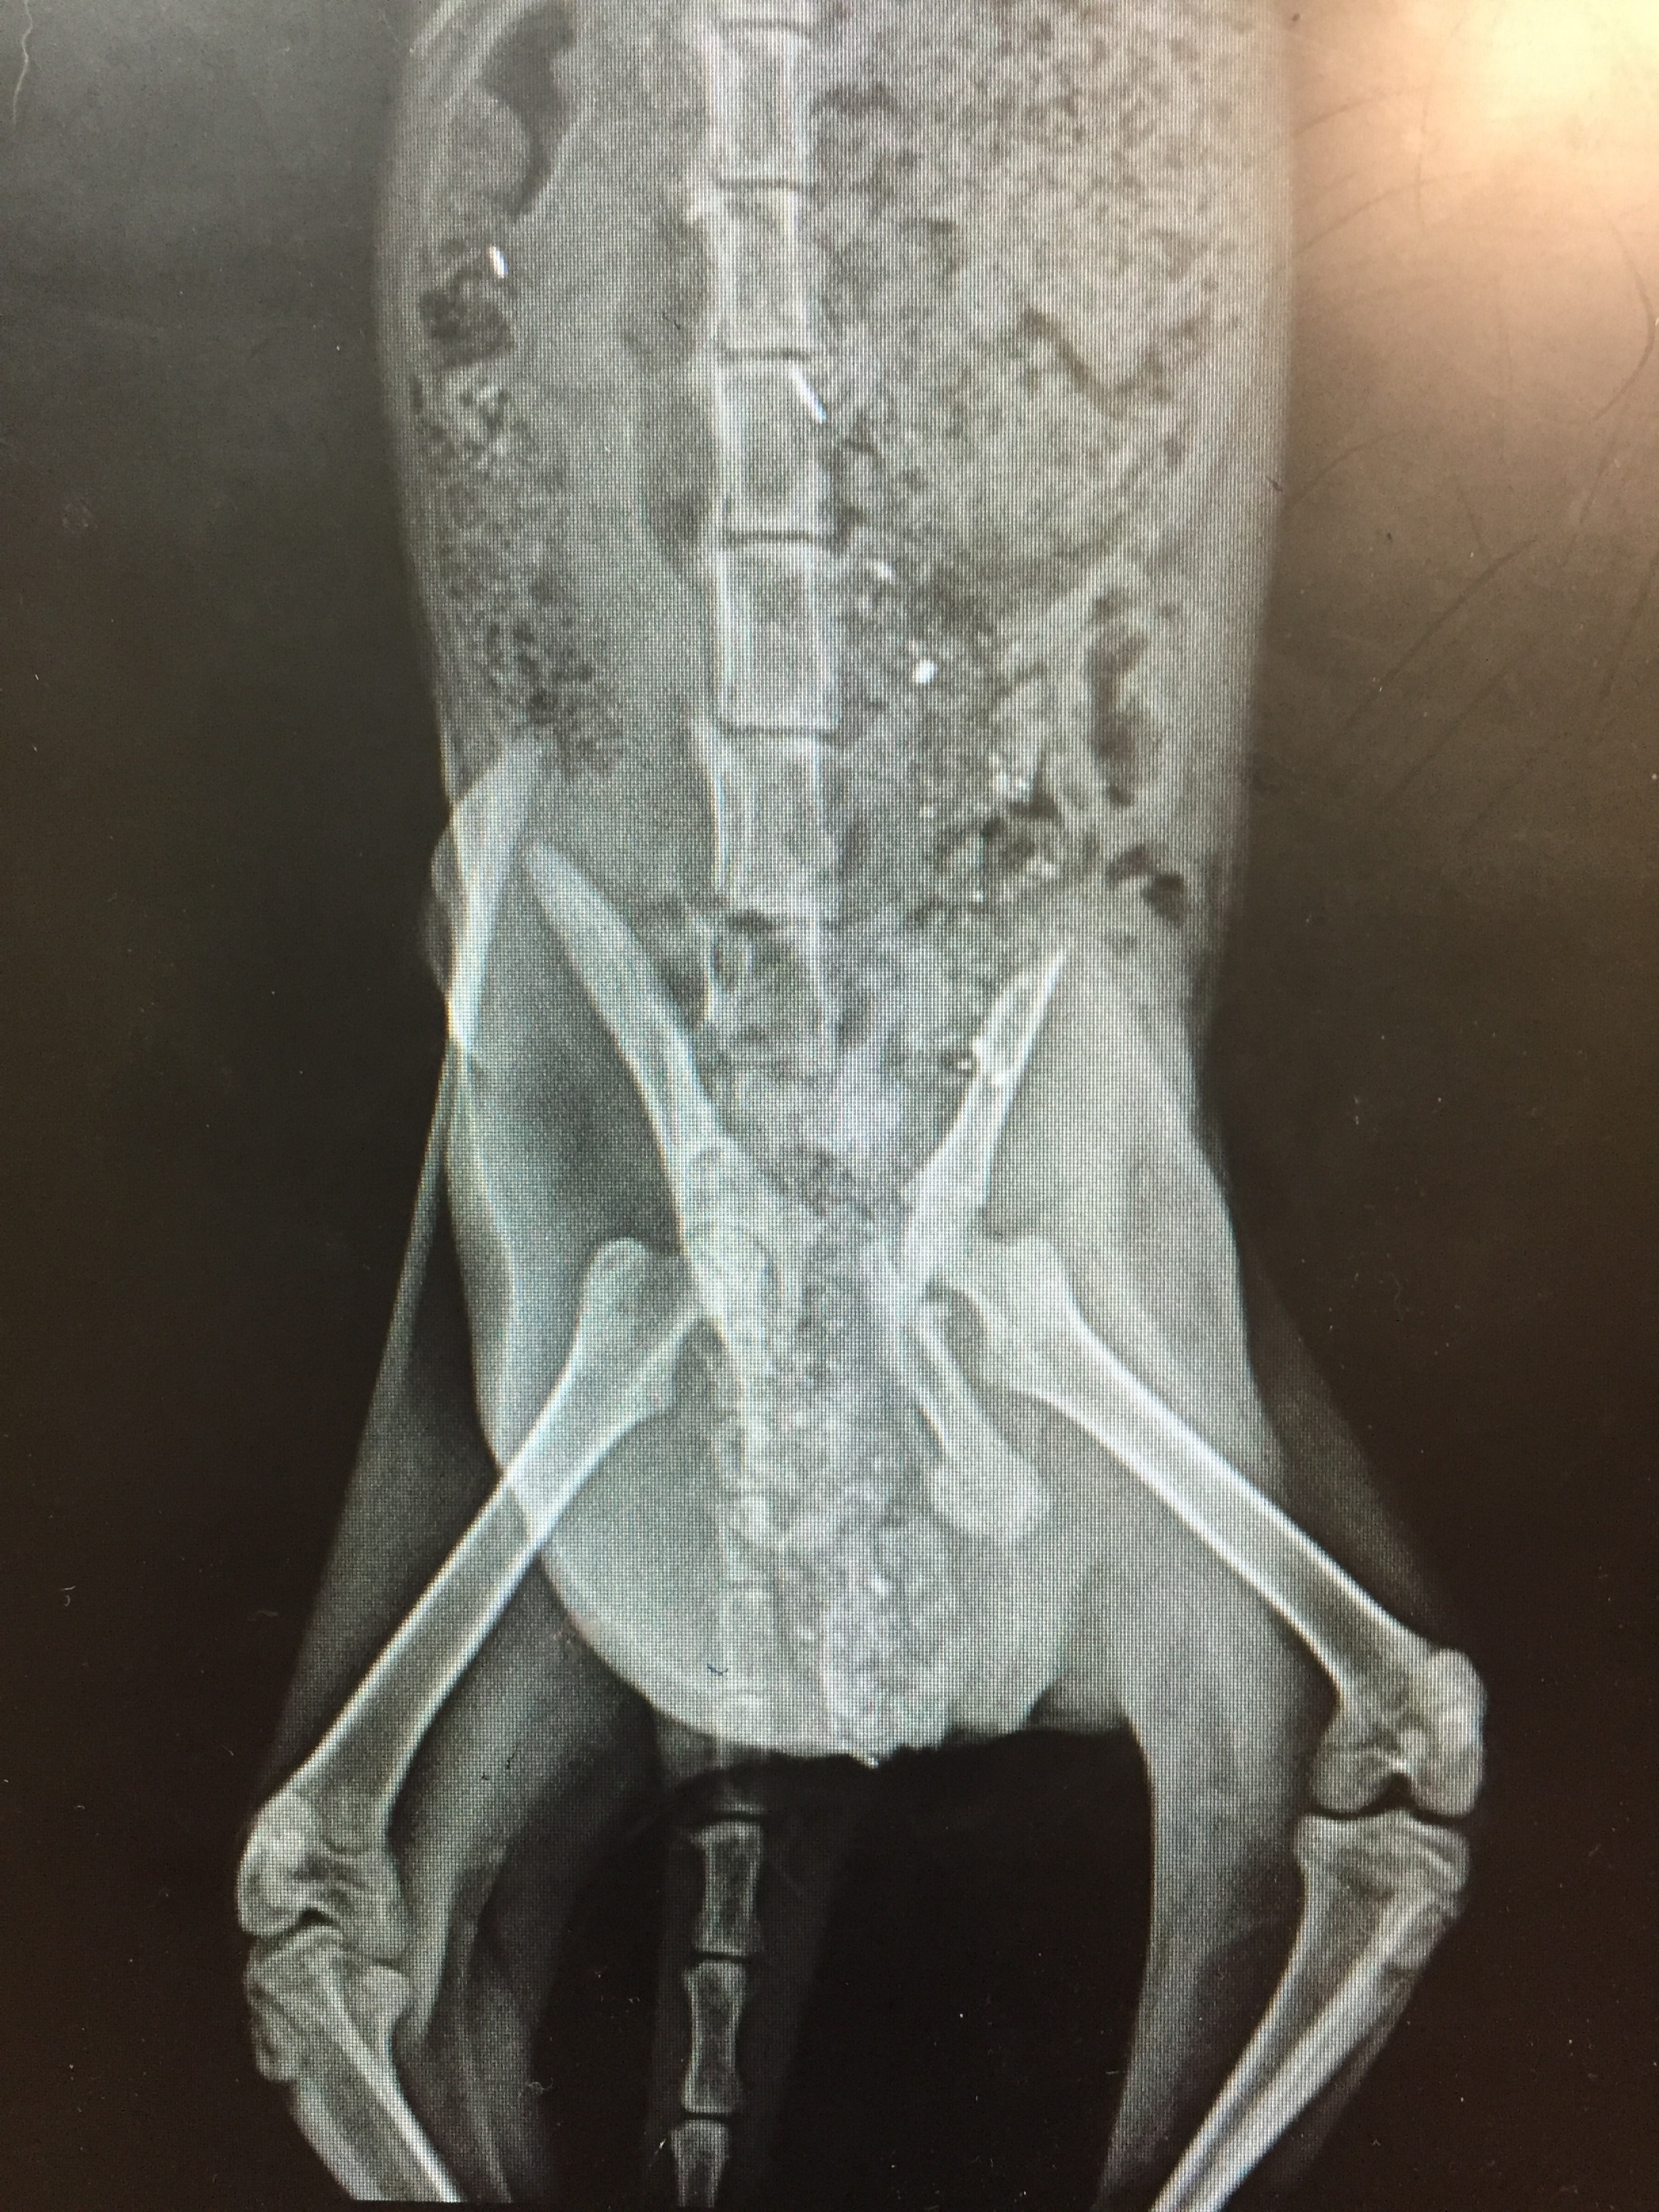

According to Dr. Harris, Cowbella has “a nasty pelvic fracture, that doesn’t seem super painful, and not much can be done surgically. She’ll likely be functional in the long run but will never walk right.” Here’s her x-ray. img_9335

He recommended she rest for about two and a half months, giving a chance for her bones to mend on their own. She should not be spayed until then either. Kim set her up in a dog crate in her house to rest. img_9331 This presents a conundrum as so far Cowbella is acting feral. Even if she stays inside for a few months until she can be spayed, she will have to definitely stay inside until spring because she won’t have her winter fur coat anymore to keep her warm. Even then, putting her back out after being inside for that long isn’t really an option. Cowbella is only about 5-6 months old – she’s not old enough to have her environment imprinted on her and remember it months later. Most likely she’ll just get used to the dog crate, which isn’t much of a life either, except for short term.

Also, we’re not sure how fast she can run to defend herself. Even worse, there’s a chance that she may not be using her back legs at all any more and is paralyzed. We think we may have trapped very soon after getting hit by a car, perhaps, and her body was still working. It is hard to tell as she does not move in front of us. But when we leave, she is eating, sometimes using the litter box, and sometimes just defecating on the papers. We can’t really get her to move so we’re looking to borrow a camera for the room.

We are grateful to Melanie for covering Cowbella’s care so far. Dr. Harris and the Elmhurst Animal Care Center are excellent and affordable. Along with the x-ray, we tested Cowbella for FIV/FeLV and she is negative. The total bill for her so far is $105. img_9381 img_9380